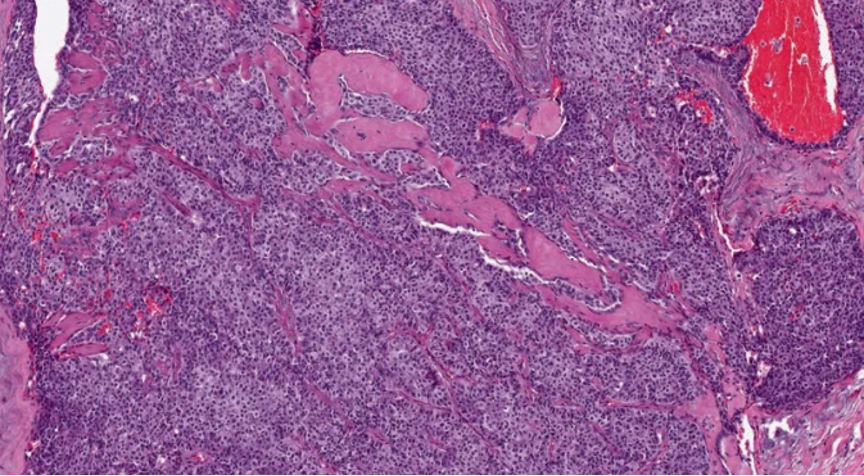

1、浸润性实性乳头状癌:保留实性乳头状结构,体积大的团巢,轮廓不规则,间质促纤维反应,肌上皮缺失,原位SPC背景

浸润性SPC

最终诊断:(右)乳腺实性乳头状癌,伴浸润,浸润成分为富于细胞的粘液癌。